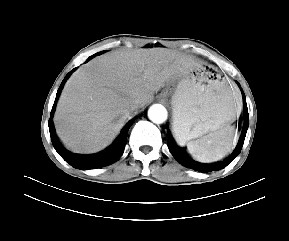

标题: CT19533:病变来源于哪?

患者,男,发现上腹部包块两月余。

病变位于肝胃间隙,实际就是位于小网膜囊(左肝下后间隙),呈轻度不均匀性强化,腹腔内及腹膜后见多发肿大淋巴结。所以我考虑肝胃间隙恶性胃肠间质瘤并淋巴结转移。

强化后病变与胃壁分界清楚,并且血供不是来源胃壁血管。考虑胰腺颈体癌并腹腔腹膜后淋巴结转移。

考虑胃肠间质瘤,病灶与胰腺分界不清,不除外胰腺肿瘤!